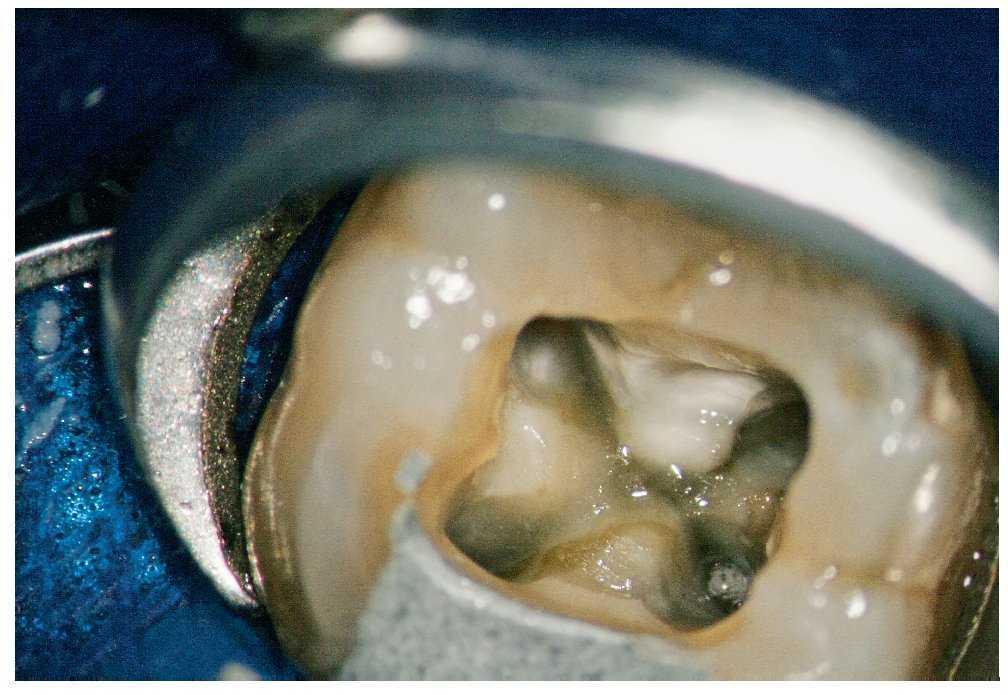

Figura 1c. Vista del suelo de la cámara pulpar después de la condensación vertical en caliente.

Figura 1d. Vista de la entrada del conducto distopalatino y de la perforación de la cámara pulpar cerrada mediante técnica adhesiva.